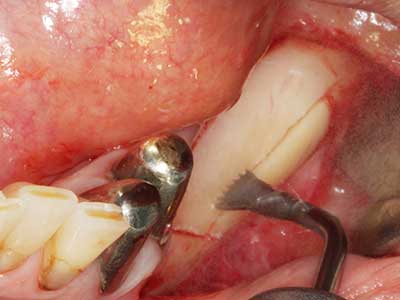

Como ya se ha mencionado, en el ámbito de la odontología conservadora también existen áreas en las que está indicada la cirugía piezoeléctrica. El uso de insertos de trabajo especiales facilita la representación del ápice radicular y, sobre todo en el área de los premolares inferiores y superiores, protege mejor los nervios y las mucosas del seno maxilar. En el caso de un cierre apical no estanco, los insertos de diamante acodados preparan de forma exacta y selectiva la cavidad de resección para el material de relleno retrógrado de la raíz. Gracias a la técnica de ultrasonidos, los insertos pueden presentar un diseño muy estilizado, lo que mejora la visión global y el tamaño de la cavidad de acceso. De este modo, en esta indicación, el uso de la cirugía por ultrasonidos se encuentra entre los métodos estándar para una apicectomía (Del Fabbro, Tsesis et al. 2010, Scarano, Artese et al. 2012).

Aplicación: Apicectomía